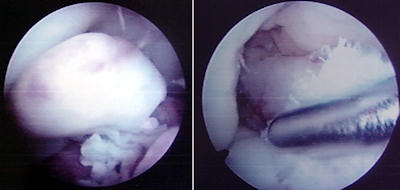

Revizyon cerrahisi diz ekleminin artroskopisi ile başlar. İlk cerrahideki greft artıkları temizlenir, eşlik eden meniskal ve kondral patolojiler düzeltilir. İlk cerrahi sırasında kullanılan implantlar, yeni tünelleri engellemiyorsa çıkartılmamalıdır. Özellikle yeni tünele yakın olan implant çıkartılırsa, tünel duvarları zayıflayabilir. Tibial tarafta çoğunlukla daha medialden bir tünel açılabilir.